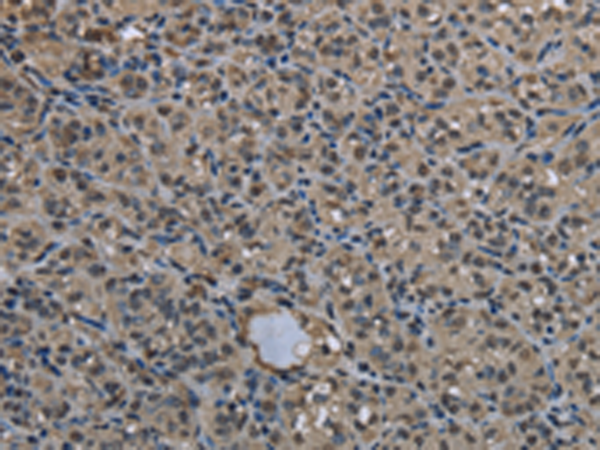

IHC positive control: |

Human thyroid cancer and Human liver cancer |

IHC Recommend dilution: |

25-100 |